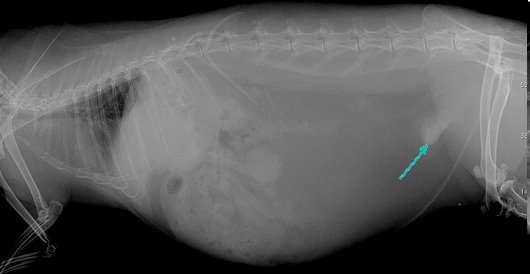

- La radiographie permet l'observation de calculs urinaires et de sablose vésicale car les cristaux et calculs formés de calcium sont très visibles à la radiographie.

Radiographie montrant une sablose vésicale chez une lapine (1)